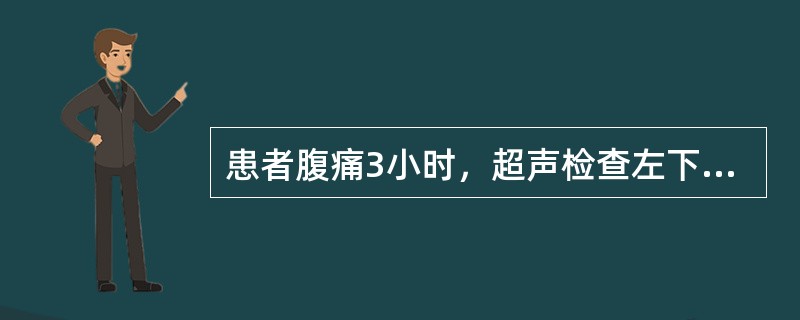

患者腹痛3小时,超声检查左下腹显像如图,诊断可能为()。

A . 肠道扩张

B . 肠道肿瘤

C . 肠套叠

D . 肠道蛔虫症

E . 肠结核